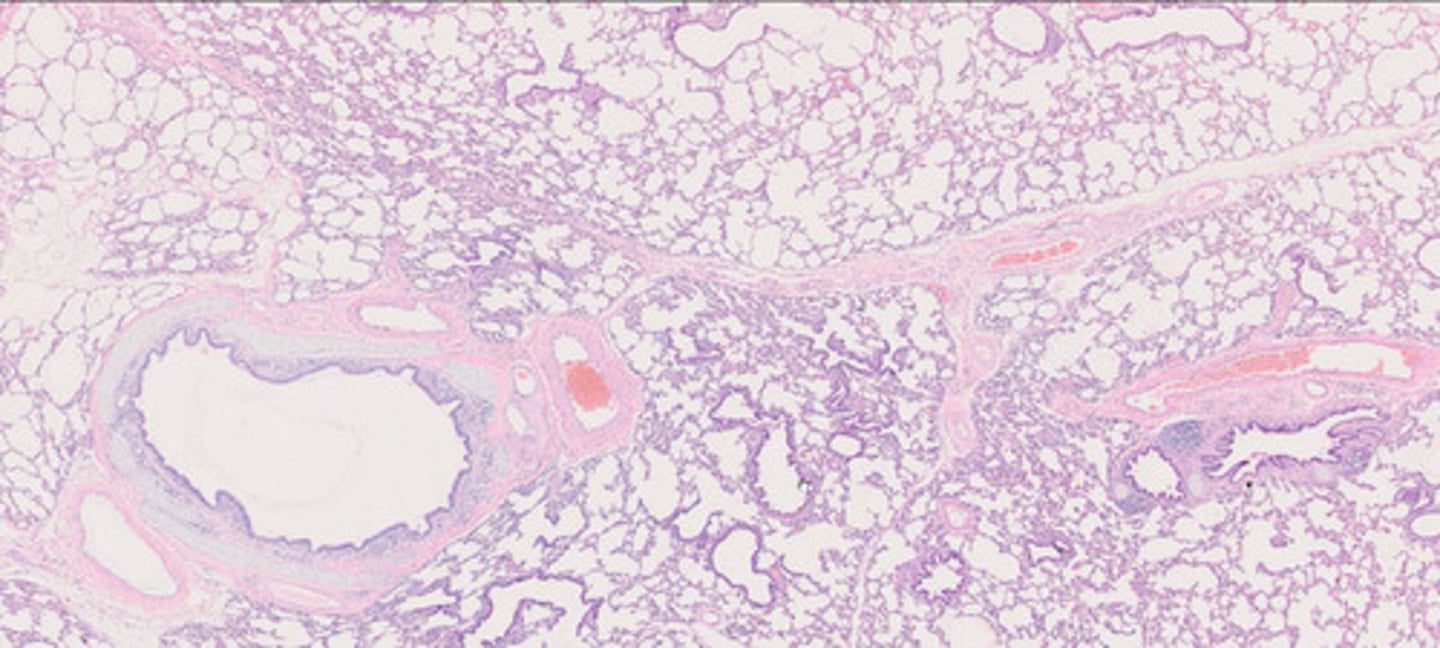

Miąższ płucny (H+E)

Tchawica (H+E)